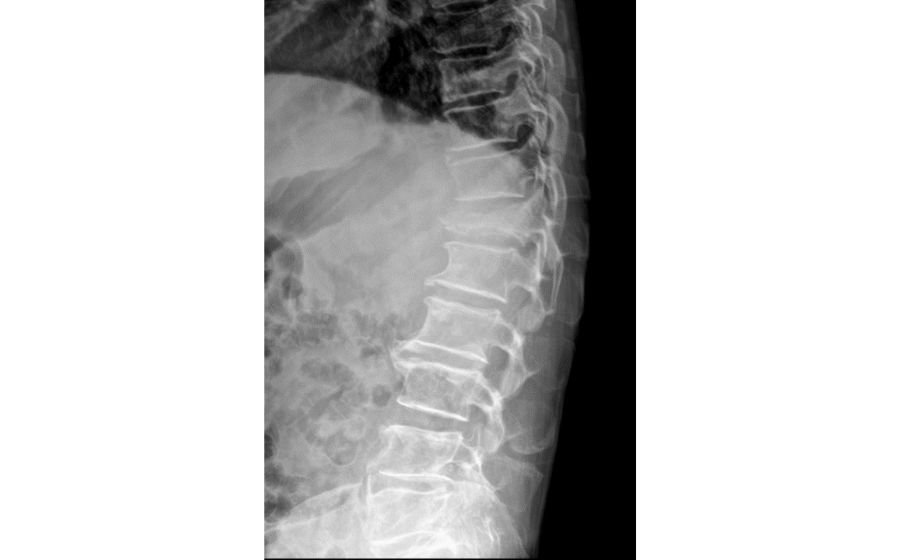

Spinal deformities occur when the spine curves abnormally—sideways in scoliosis or forward in kyphosis. These changes can affect posture, balance, back pain, and sometimes breathing. Children may develop scoliosis during growth, while adults often develop deformity from degeneration, arthritis, or previous spine problems. Evaluation includes full-length X-rays and alignment analysis. Treatment depends on curve severity: smaller curves are observed, moderate curves may need bracing, and larger curves can require corrective surgery. Advanced modern techniques ensure safer correction, improved alignment, and long-term functional recovery.